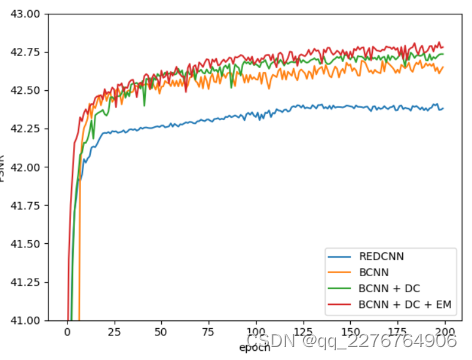

1)结构和模块:为了探究EDCNN模型各组成部分的作用,我们对结构进行了分解实验。 首先,我们设计了一个基本模型(BCNN),从图1所示的结构中去除了密集连接和边缘增强模块,然后添加了密集连接(BCNN+DC)和边缘增强模块(BCNN+DC+EM, EDCNN)依次。 为了充分展示模型的潜在能力,所有模型都使用相同的训练策略进行 MSE 损失训练。

图 5 显示了 PSNR 曲线,在每个时期对训练模型的测试集进行测试。 我们还添加 REDCNN 作为比较。 值得注意的是,我们设计的基本模型(BCNN)已经取得了比 REDCNN 更好的性能。 并且通过添加密集连接和边缘增强模块,PSNR的值将不断增加。 此外,边缘增强模块加速了模型的收敛过程。 在表中。 III,我们可以检查这些模型的 PSNR、SSIM、RMSE 值。 完整的 EDCNN 模型在这些指标上具有最佳结果。